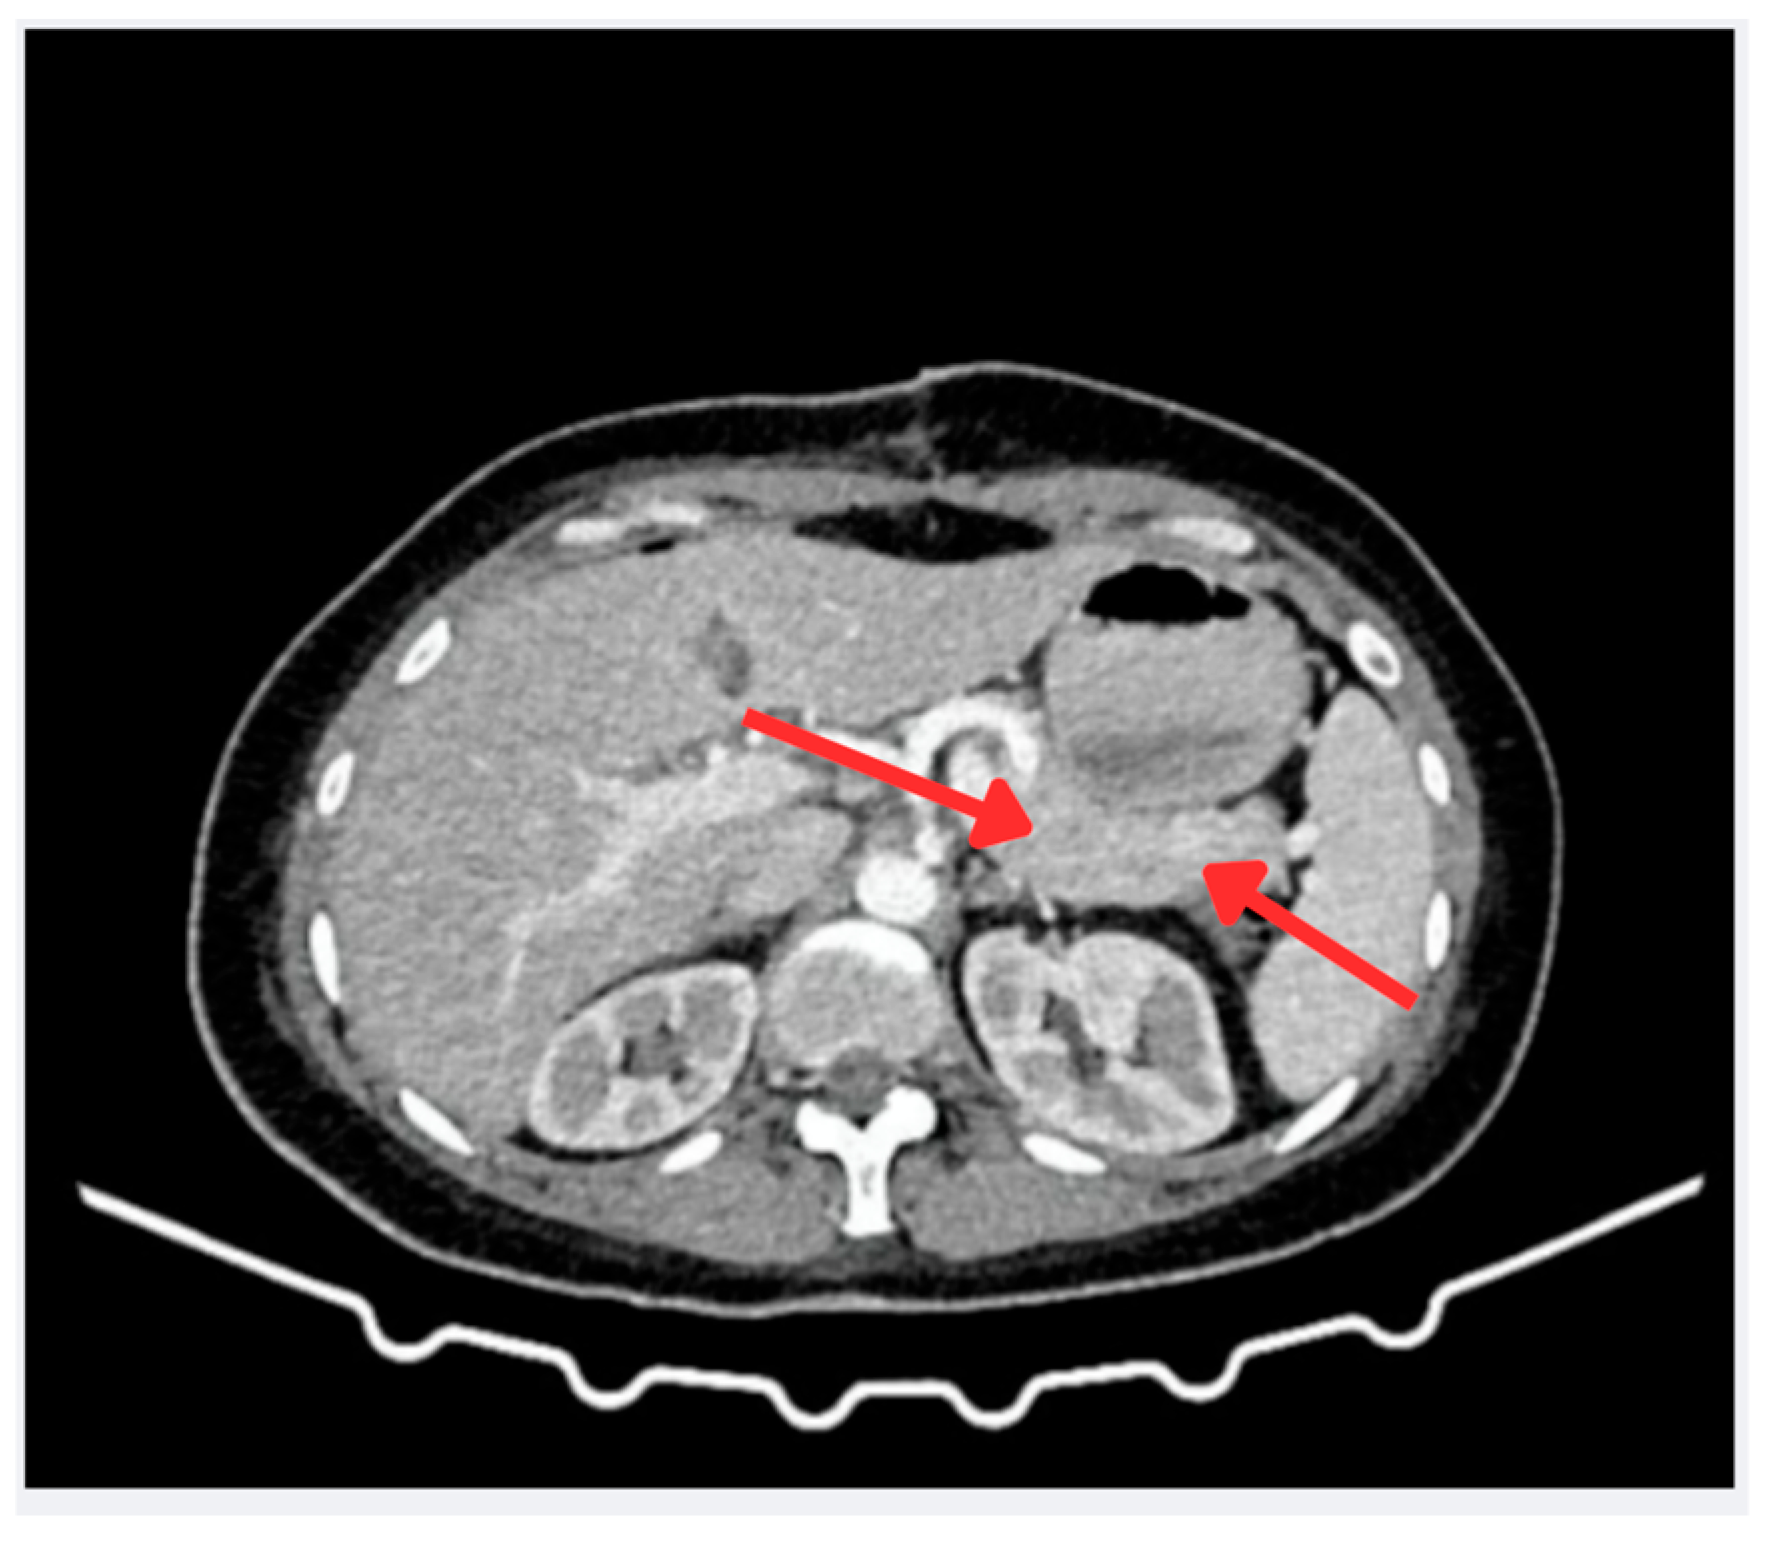

A contrast-enhanced abdominal CT scan with pancreatic protocol (arterial and venous phases) revealed no abnormalities (Figure 2). Finally, endoscopic ultrasound was the modality that identified a hypoechoic lesion in the uncinate process of the pancreas, leading to targeted biopsies.

Figure 2.

Contrast-enhanced abdominal CT scan (portal phase). Axial view showing the pancreatic region. The red arrows discreetly indicate the area of interest, where no significant abnormalities in density or enhancement are observed in the pancreas or portosplenic region. Based on these imaging findings, no evidence of a neuroendocrine tumor was identified at this stage.